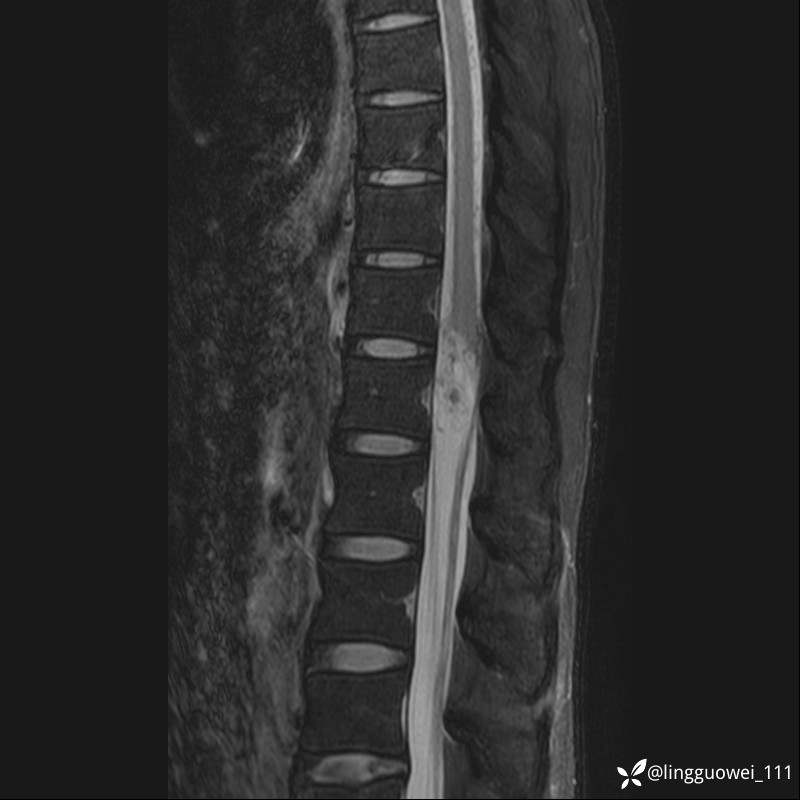

男,38岁,反复腰痛伴双腹股沟区痹痛半年,加重1月。

腰椎MR,注意脊髓异常信号,与伪影鉴别,一不小心就会漏诊